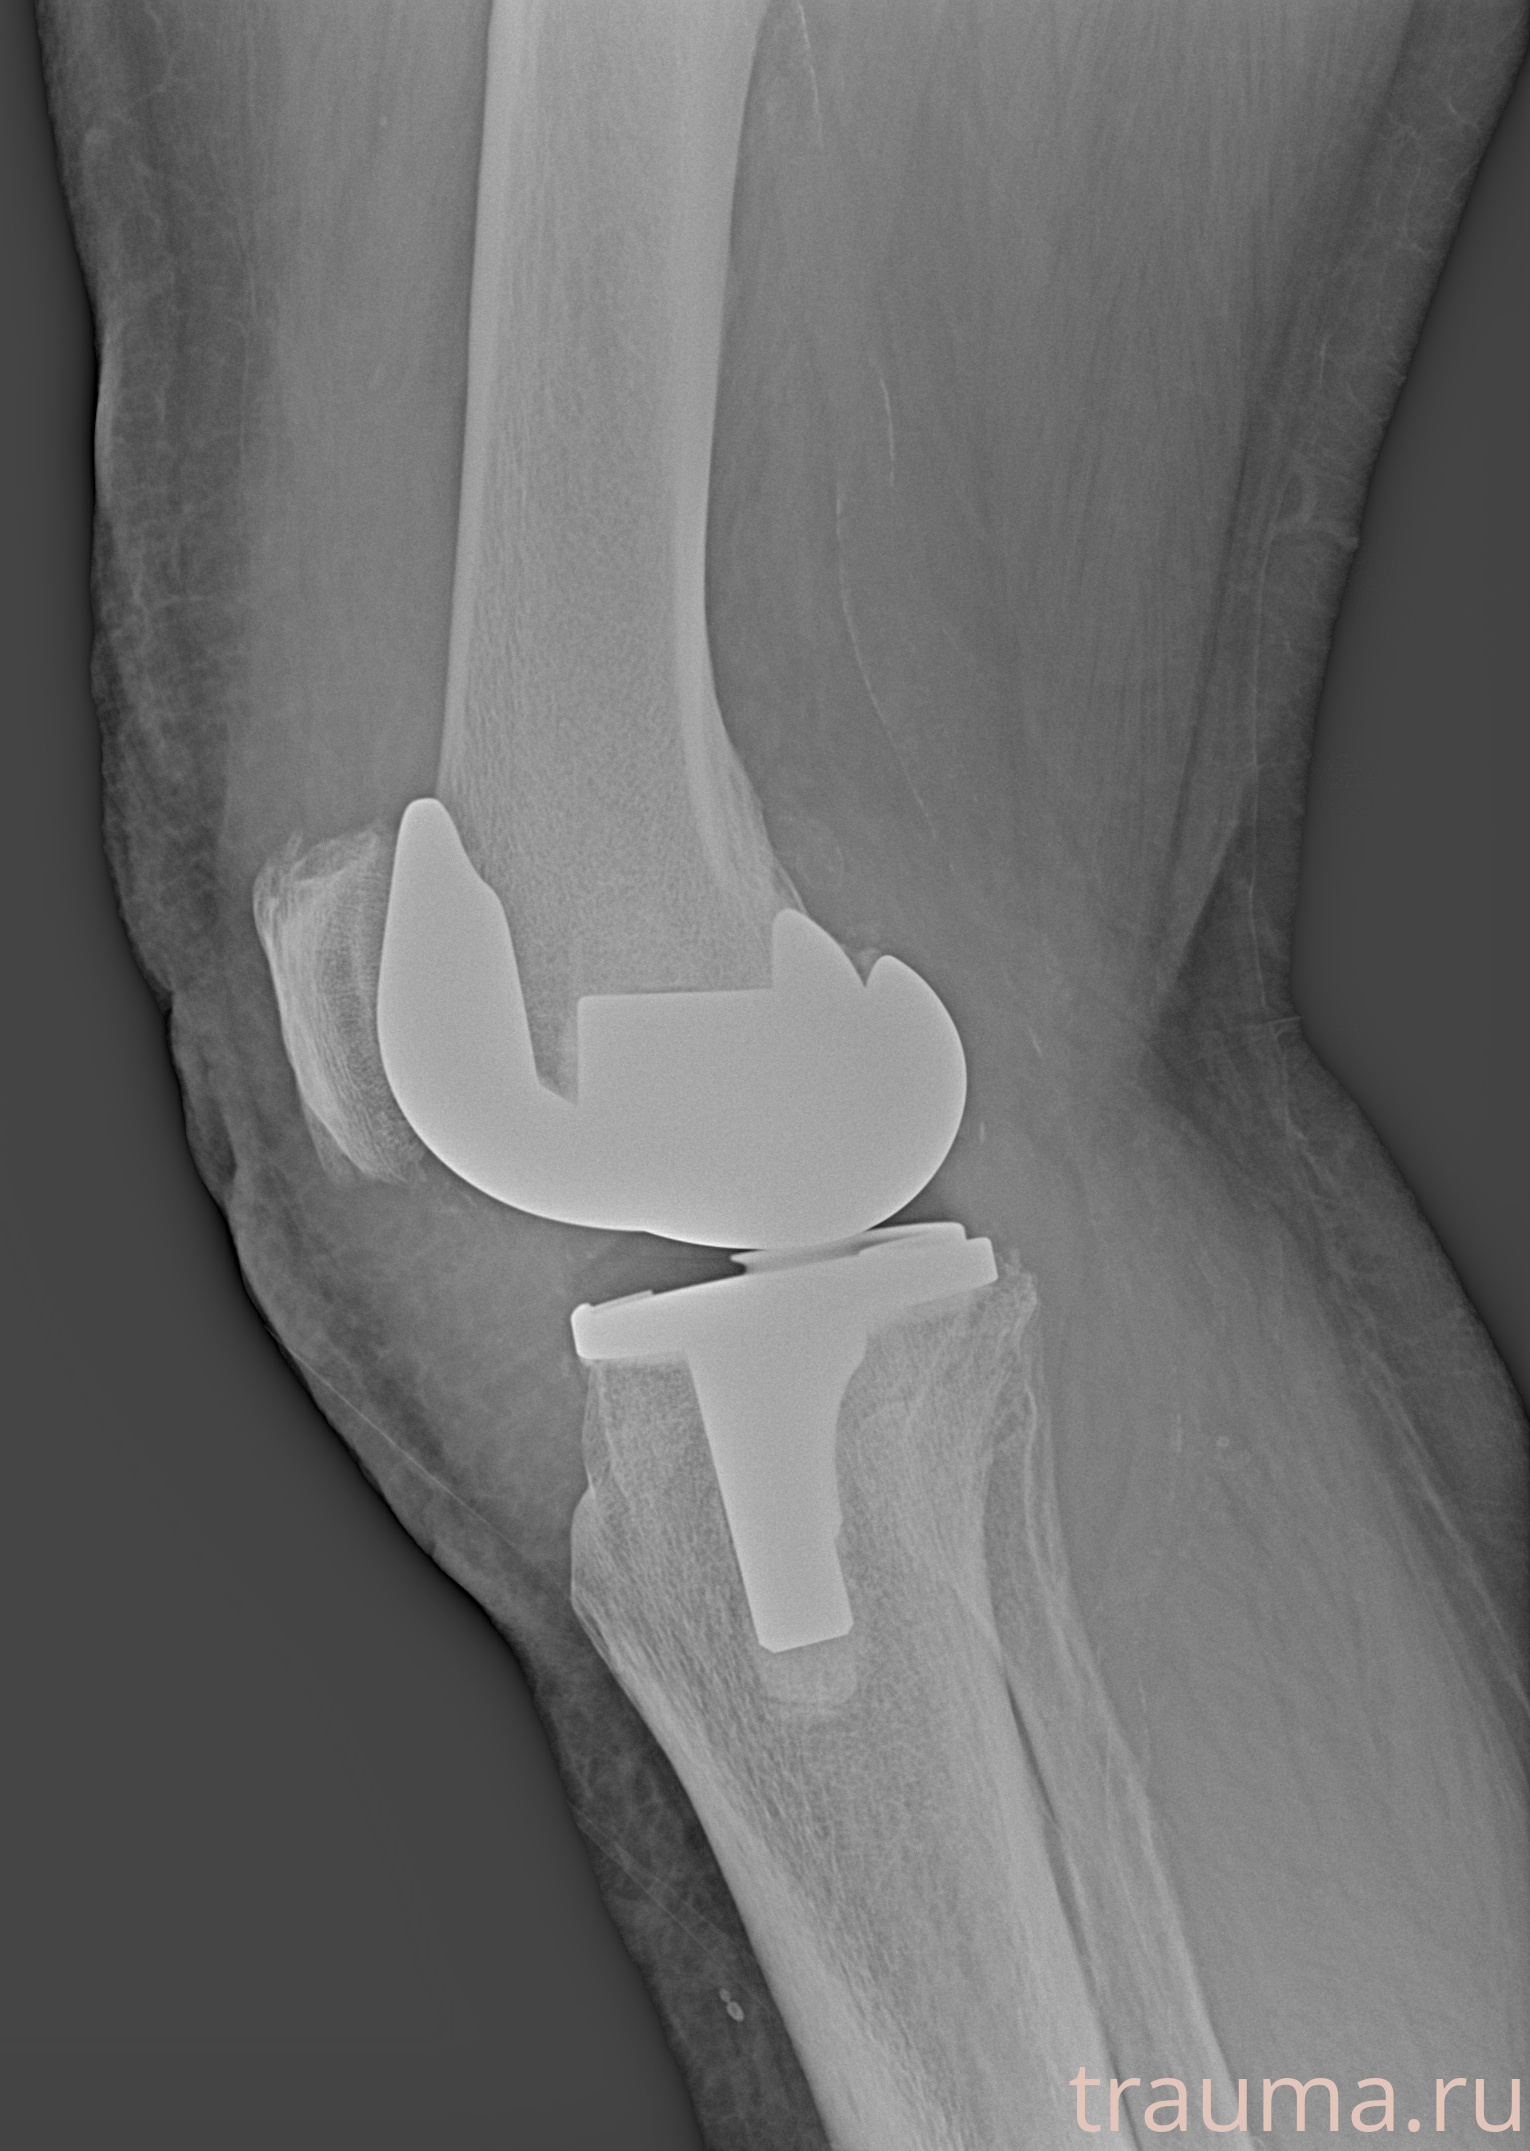

Правый

Рентгенограммы